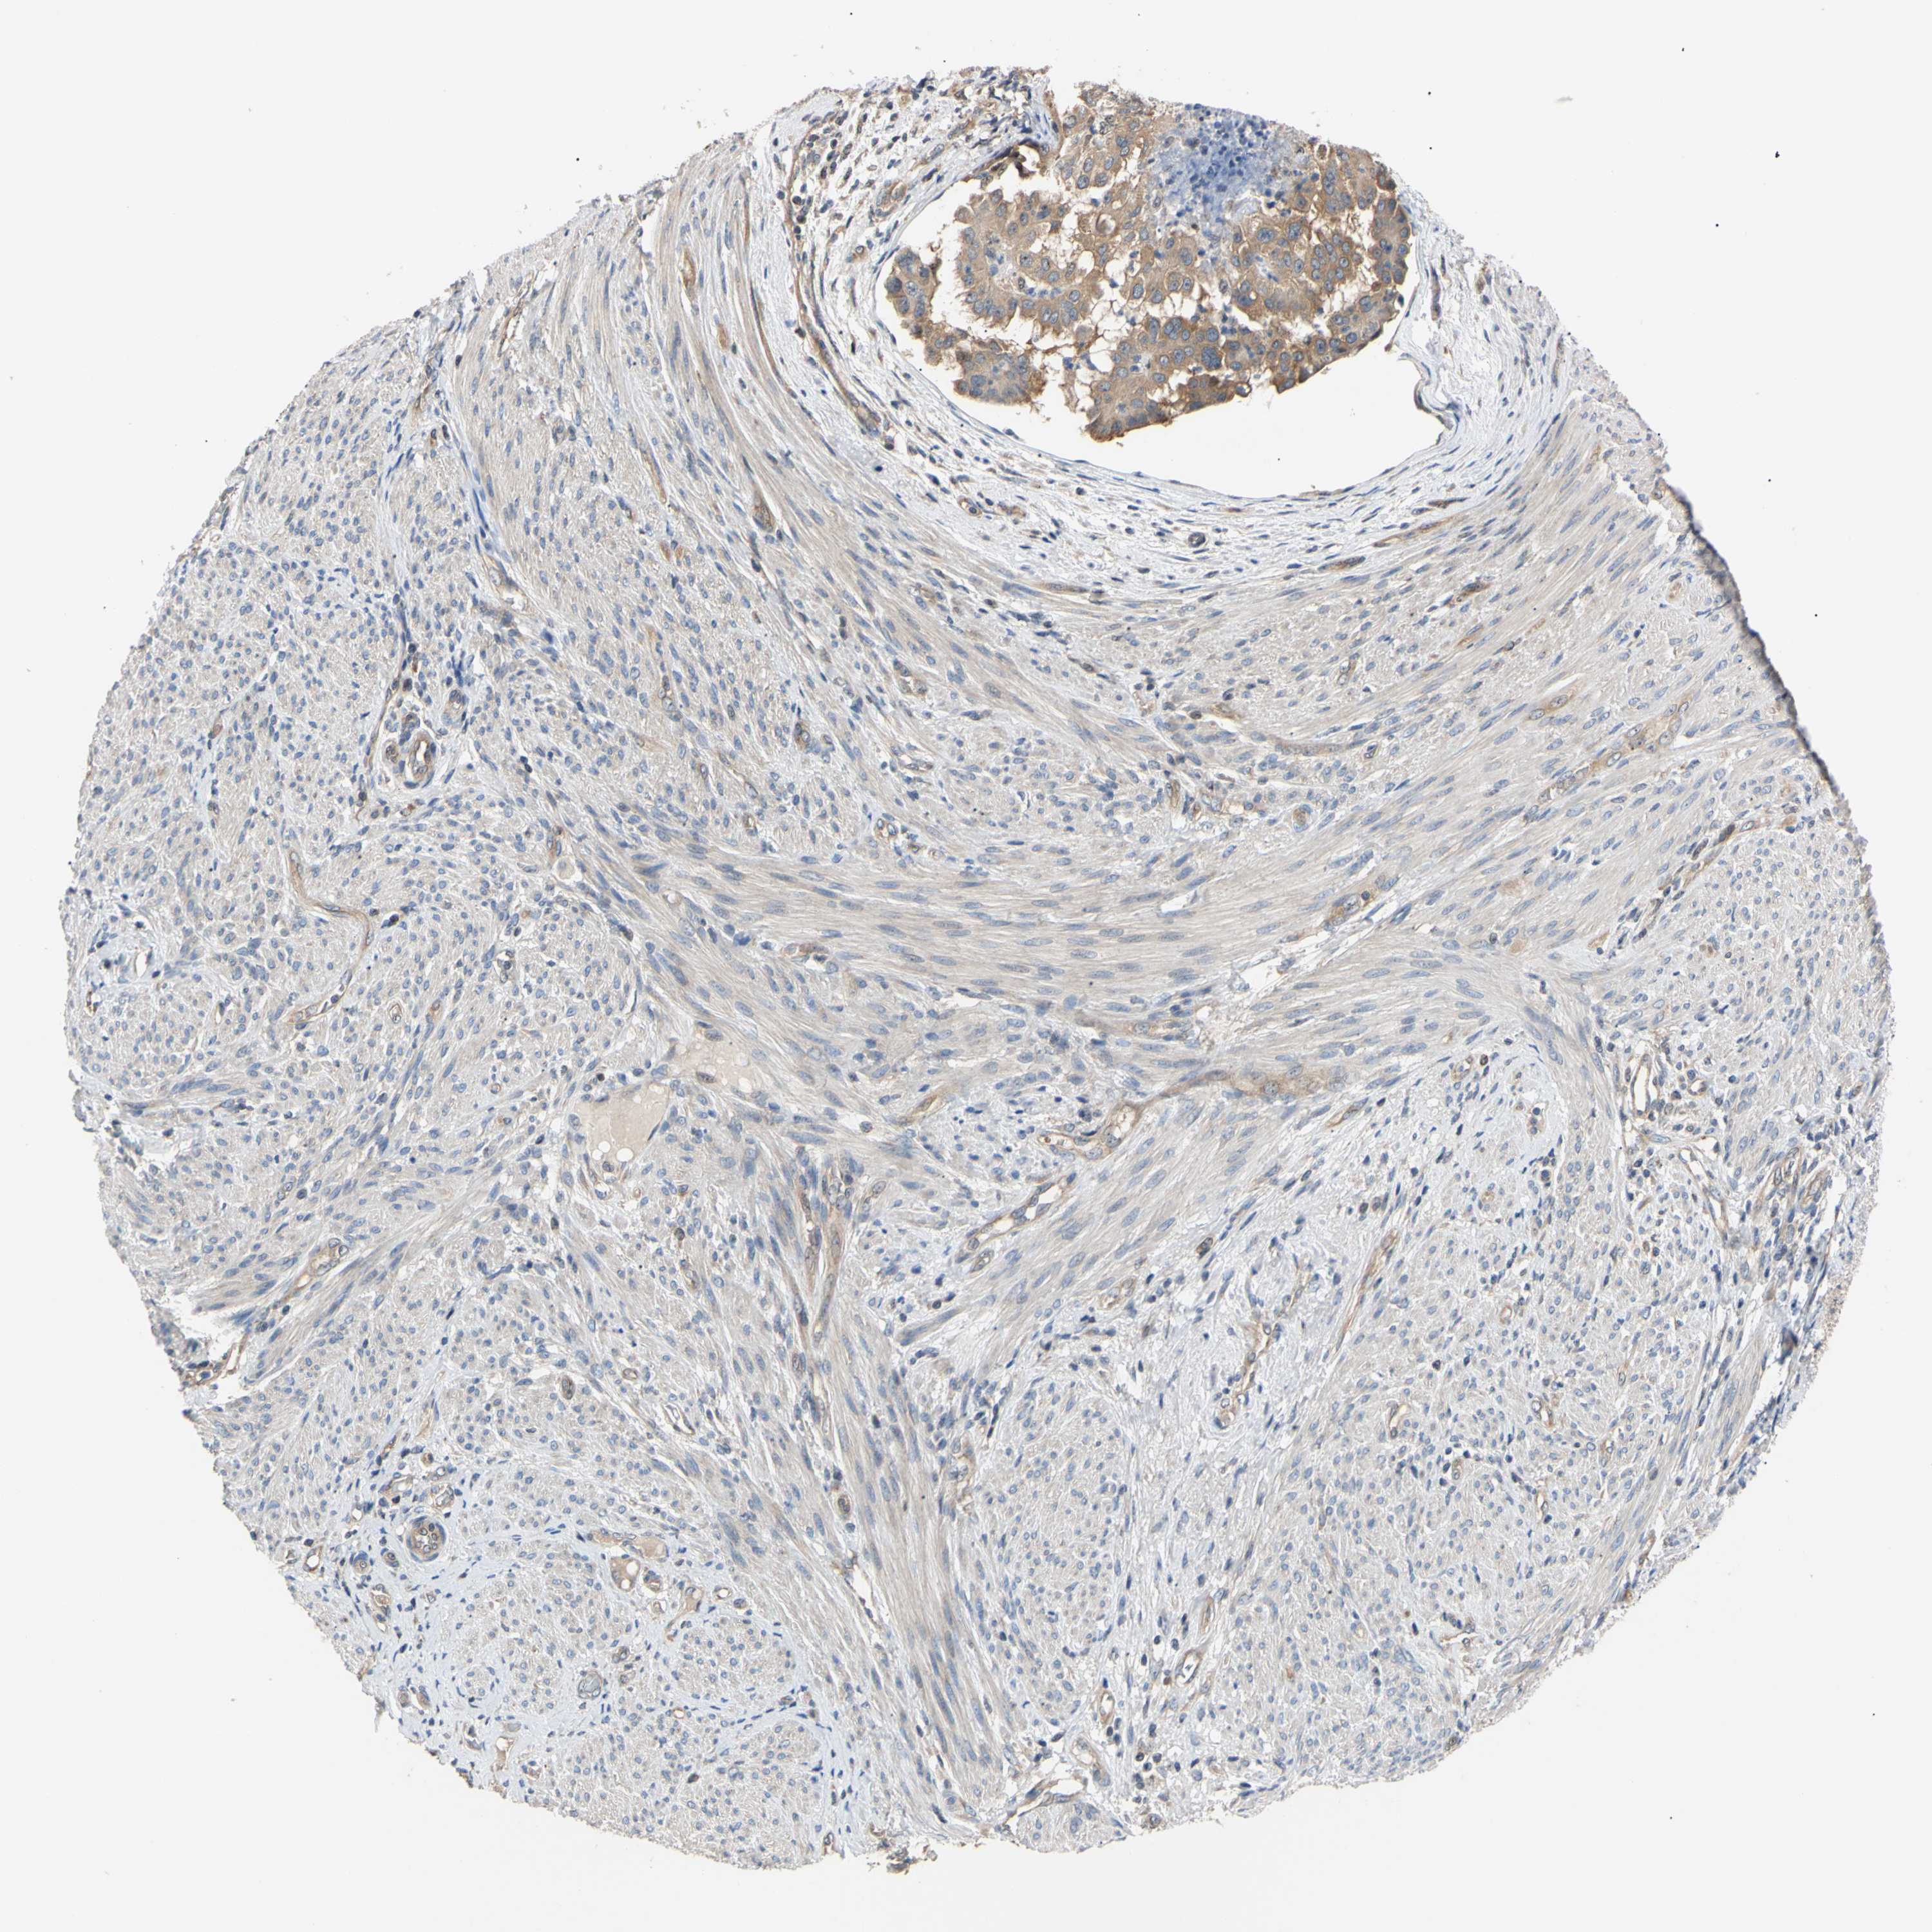

ENDOMETRIAL CANCER - Protein expressioni

A mouse-over function shows sample information and annotation data. Click on an image to view it in a full screen mode. Samples can be filtered based on level of antibody staining by selecting one or several of the following categories: high, medium, low and not detected. The assay and annotation is described here.

Note that samples used for immunohistochemistry by the Human Protein Atlas do not correspond to samples in the TCGA dataset.

Antibody stainingi

Antibody staining in the annotated cell types in the current human tissue is reported as not detected, low, medium, or high, based on conventional immunohistochemistry profiling in selected tissues. This score is based on the combination of the staining intensity and fraction of stained cells.

Each image is clickable and will lead to virtual microscopy that enables deeper exploration of all samples and also displays staining intensity scores, fraction scores and subcellular localization as well as patient and tissue information for each sample.

Antibody HPA003979

Antibody HPA004130

Staining

High

Medium

Low

Not detected

Intensity

Strong

Moderate

Weak

Negative

Quantity

>75%

75%-25%

<25%

None

Location

Nuclear

Cytoplasmic/membranous

Cytoplasmic/membranous,nuclear

Adenocarcinoma, NOS

Neoplasm, malignant, NOS